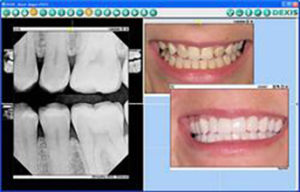

“Where children and radiation are concerned, I’m convinced that it is our responsibility to minimize their exposure. Since digital radiography requires less radiation than traditional film, it’s a step in the right direction. When you’re working with children, you’re also working with their parents. I’ve found that digital radiography increases my patient and parent education because I can use enlarged images to increase their understanding of disease and treatment (Fig. 3).